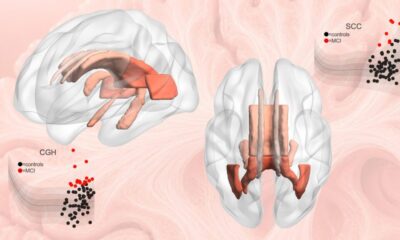

Uncategorized1 week agoDisease Detection Gets Boost from Keck’s New Brain Reference Map

Investigators at the USC Mark and Mary Stevens Neuroimaging and Informatics Institute (Stevens INI) at the Keck School of Medicine say they have created one of...